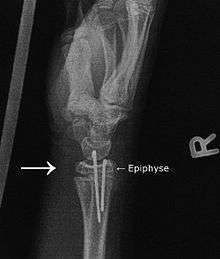

Osteosynthesis is the reduction and internal fixation of a bone fracture with implantable devices that are usually made of metal. It is a surgical procedure with an open or per cutaneous approach to the fractured bone. Osteosynthesis aims to bring the fractured bone ends together and immobilize the fracture site while healing takes place. In a fracture that is rigidly immobilized the fracture heals by the process of intramembranous ossification.